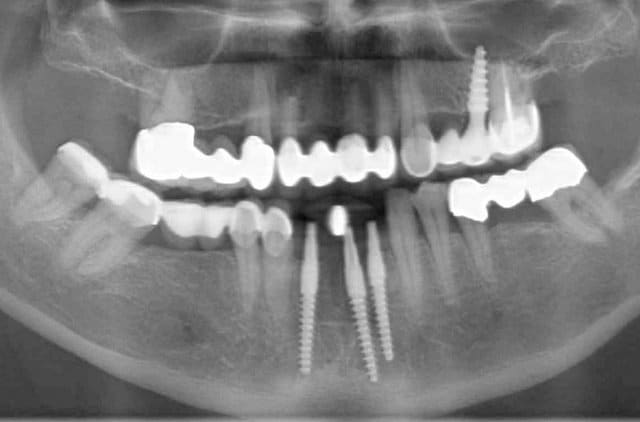

Pour la distance inter-implants c est une bonne remarque, le distance réglementaire est de 2/3mm en méthode conventionelle , ici c´est une variante du flapless en forant de manière à condenser l´os via un foret à 3 faces. En préservant le périoste on a remarqué que cette distance réglementaire pouvait être plus petite. C est une observation , qui marche (en flaples) dans ma pratique et dans celles de mes confrères Allemands, à ma connaissance pas enormément documenté . Ceci dit il y a un livre en francais qui en parle "implantologie flapless" de Byung Ho Choi et wilfried Engelke (Pr de Göttingen).

Sur le cas posté au début la dernière radio est après deux ans post OP. Ci dessous un autre exemple.

Les 12 premières photos sont un même cas avec implantation immédiate.

Le deuxième cas c est les photos 13 14 15 , (la photo 14 et 15 est après 5 ans)

Le dernier cas (3 dernieres photos), a été realisé il y a 5 ans il n y a pas de problème, je ne trouve pas les radios malheureusement je vais chercher encore un peu dans la journée.